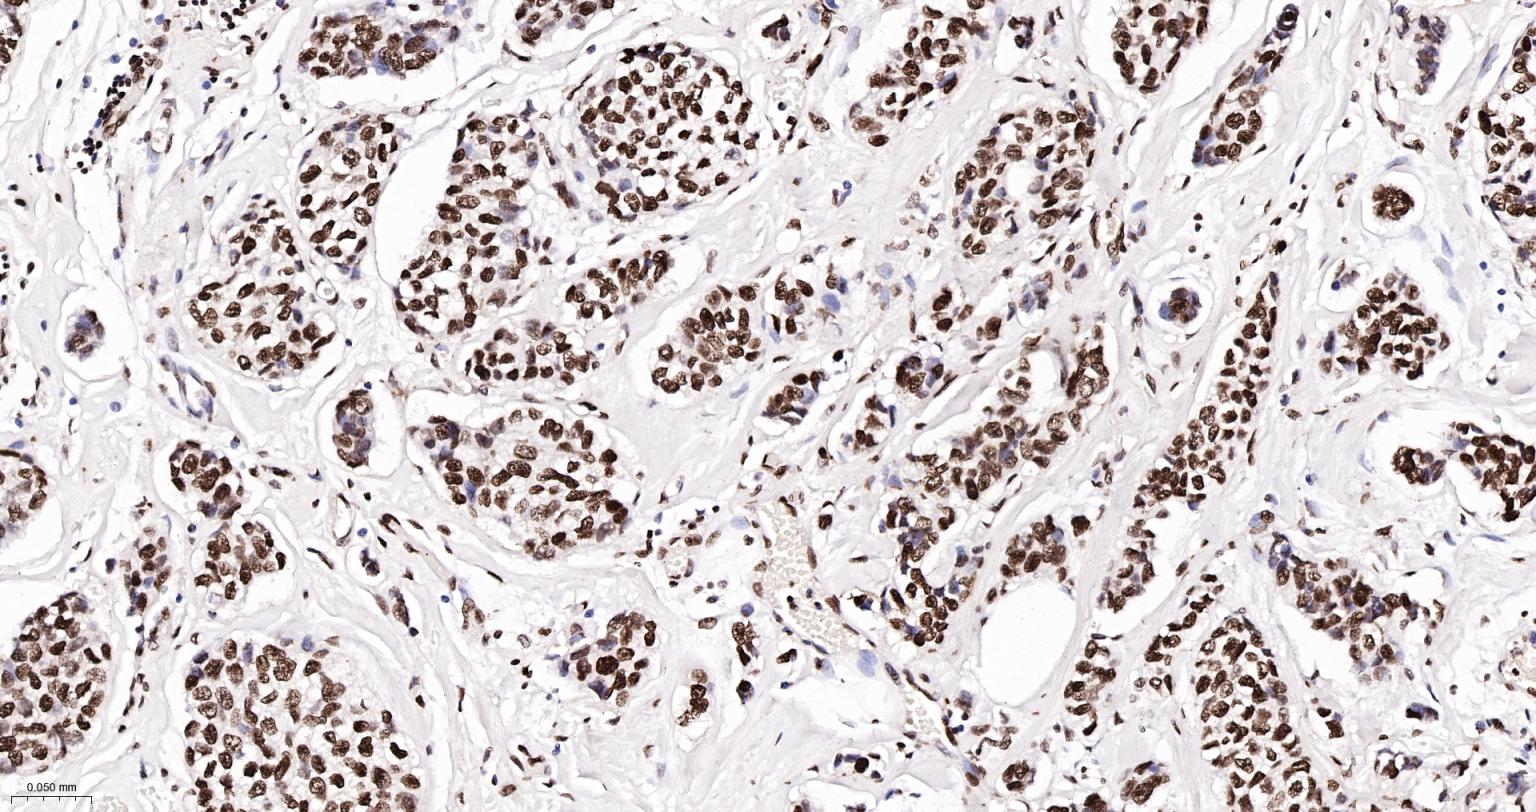

Paraformaldehyde-fixed, paraffin embedded Human Breast Cancer; Antigen retrieval by boiling in sodium citrate buffer (pH6.0) for 15 min; Antibody incubation with Histone H2A.X Monoclonal Antibody, Unconjugated(bsm-61080R) at 1:200 overnight at 4°C, followed by conjugation to the SP Kit(Rabbit, SP-0023) and DAB (C-0010) staining.